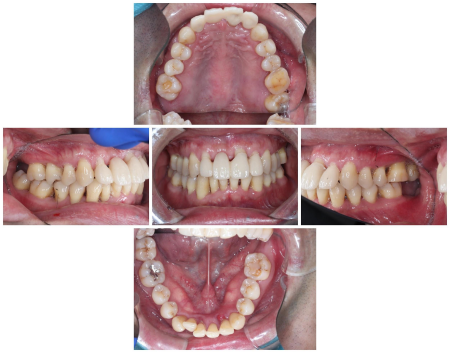

治療中

まず、歯ぐきの内側を清掃する「縁下スケーリング」と、歯ぐきを開いて歯の根を直接見ながら綺麗にする「フラップ手術」を行い、上の前歯のプラークや歯石、感染物を徹底的に取り除きました。

その後、歯に専用のパウダーを吹き付ける「エアーフロー」によるクリーニングを2週に1回の頻度で行い、出血のない歯ぐきを目指しました。

歯ぐきの回復が認められた段階で前歯を確認した結果、特に揺れが強かった右上の前歯1本以外は残せると判断しました。

そこで、温存が難しい歯を抜いてから、その隣の右上の前歯1本(側切歯/2番)と左上の前歯2本(中切歯、側切歯)を連結して橋渡しのように歯を補う被せ物「ブリッジ」で治療する方法をご案内し、ご希望いただきました。

被せ物治療の際は、歯を1本ずつ丁寧に削って土台の形に整え、まずは1段階目の仮歯を装着しました。

土台の形を微調整した後、口腔内の写真撮影と型取りを行い、患者様のご希望を考慮した形の本格的な仮歯を再度作製しました。